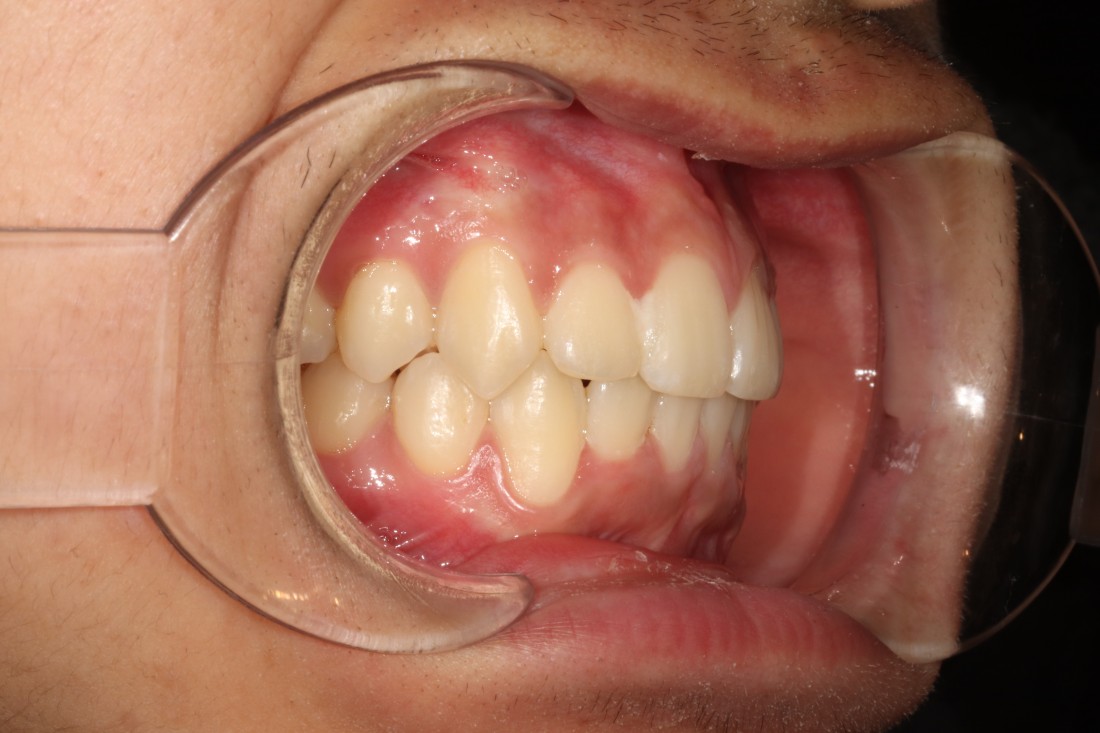

과개교합 이란?

윗니가 아랫니를

과하게 덮는 부정교합으로,

아래치아가 윗니에 가려

거의 보이지 않습니다.

윗니에 아랫니가 거의 덮여있는

과개교합의 경우에는

턱관절 장애를 유발합니다.

윗니가 아랫니를 거의 덮어서

보이지 않을 정도의 부정교합의 종류인데요.